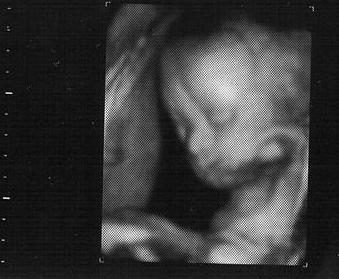

Just got back from 3D sonogram at Impact!!

Here she is!!

Image Attachment(s):